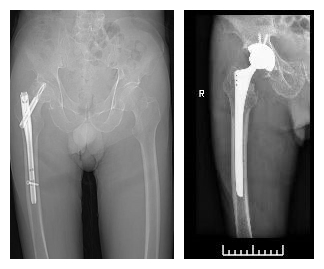

股骨粗隆间骨折术后股骨头坏死关节翻修手术